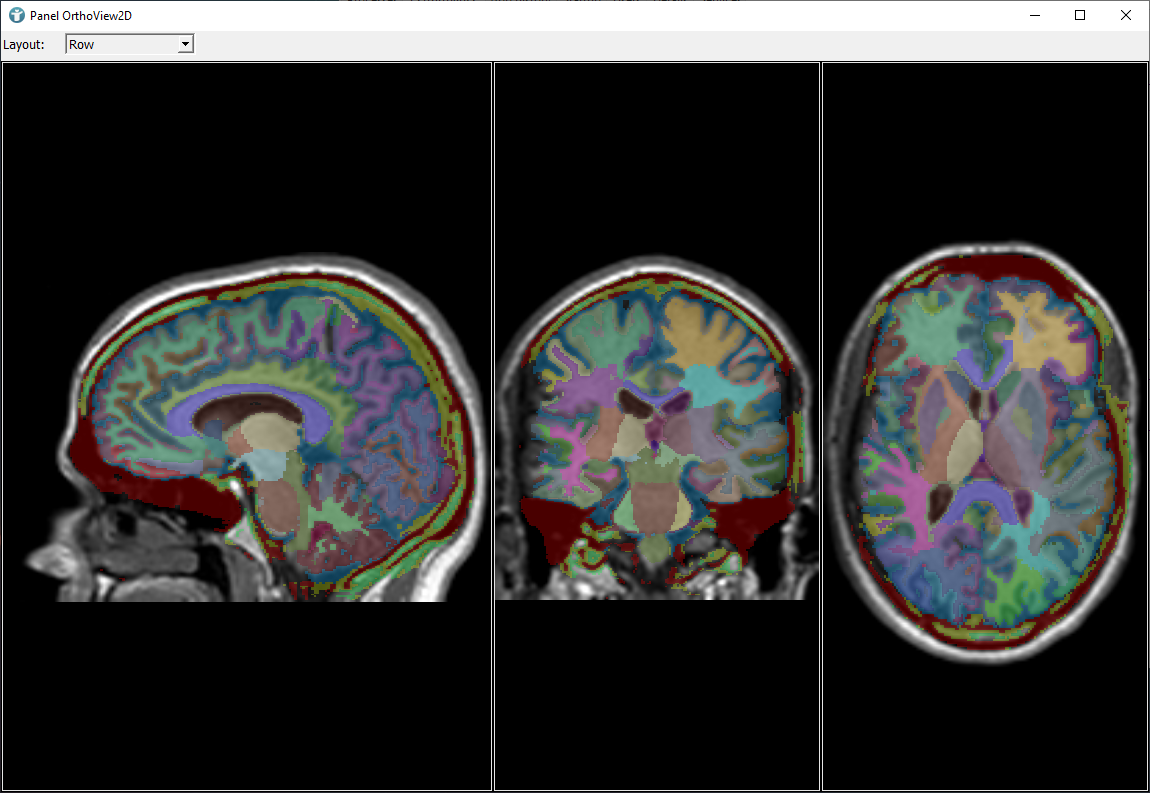

Add an OrthoView2D module to your network and save the .mlab file.

Without adding a SubImage, the segmentation results should look like this: